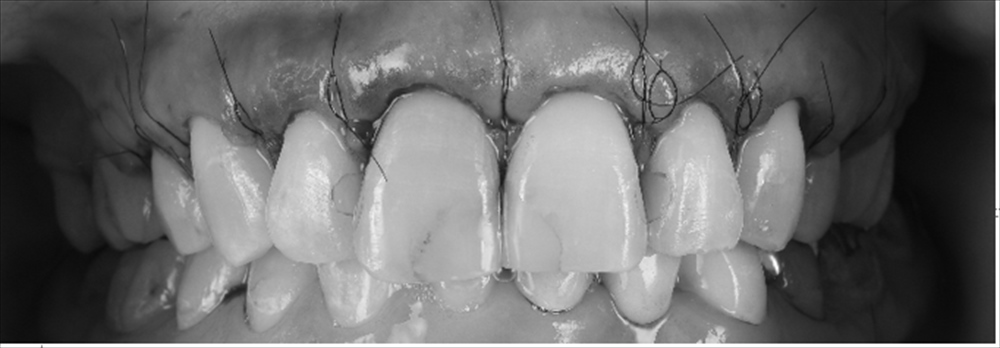

確かに前歯は今まで詰めてきた詰め物が割れ、変色をし神経がない事もあり右上の前歯は色が変わっています。歯茎が見えるガミースマイルだった為、歯肉形成外科をマイクロサージェリーで行い

歯の長さを獲得しました。